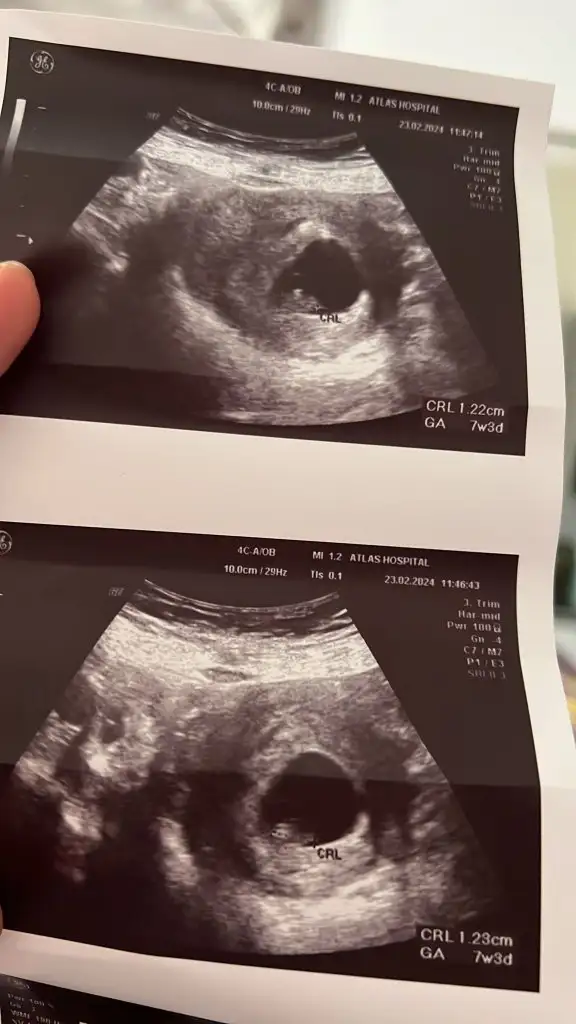

Cinsiyet tahmini alabilir miyim

Eklentiler

• IMG_20240219_161530.webp

IMG_20240219_161530.webp

23,7 KB · Görüntüleme: 71